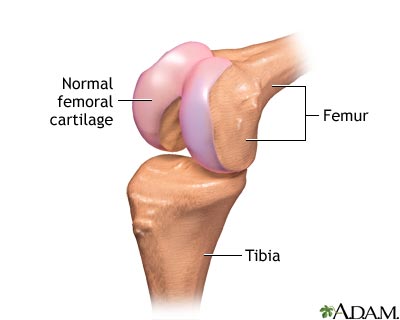

The structure of a joint - illustration

The structure of a joint

illustration